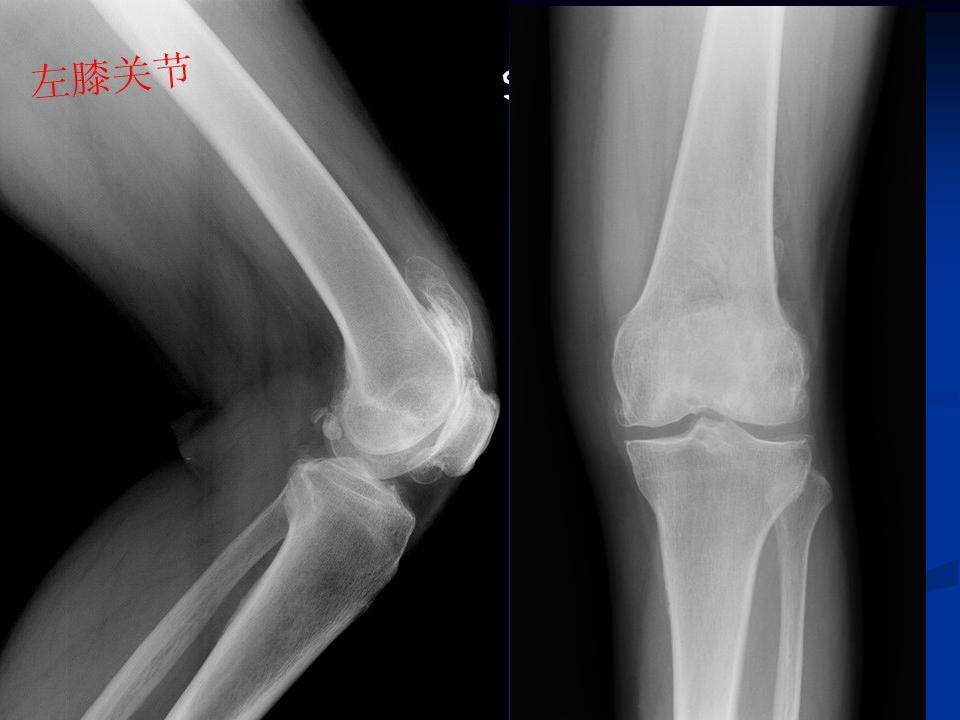

膝关节退行性变(半月板钙化、膝关节变形)